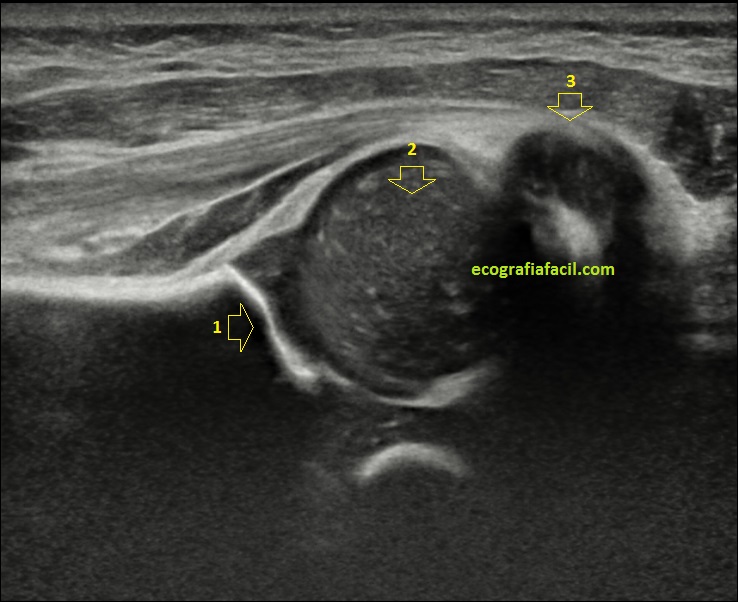

La imagen 3 te marca exploración nítida sin movimiento, la imagen 4 todo lo contrario. Las zonas numeradas son acetábulo, cabeza femoral y trocánter, obsérvalas tu misma y verás como en la imagen 4 todo está borrado, llama muchísimo la atención la cabeza femoral, que está capturada en pleno movimiento, con artefacto cinético clarísimo.